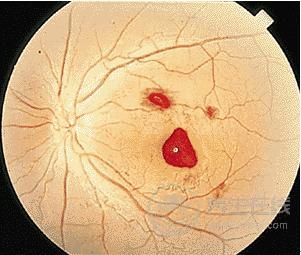

2、四肢無力、眼底出血,不是肝血虛弱就是肝火過剩